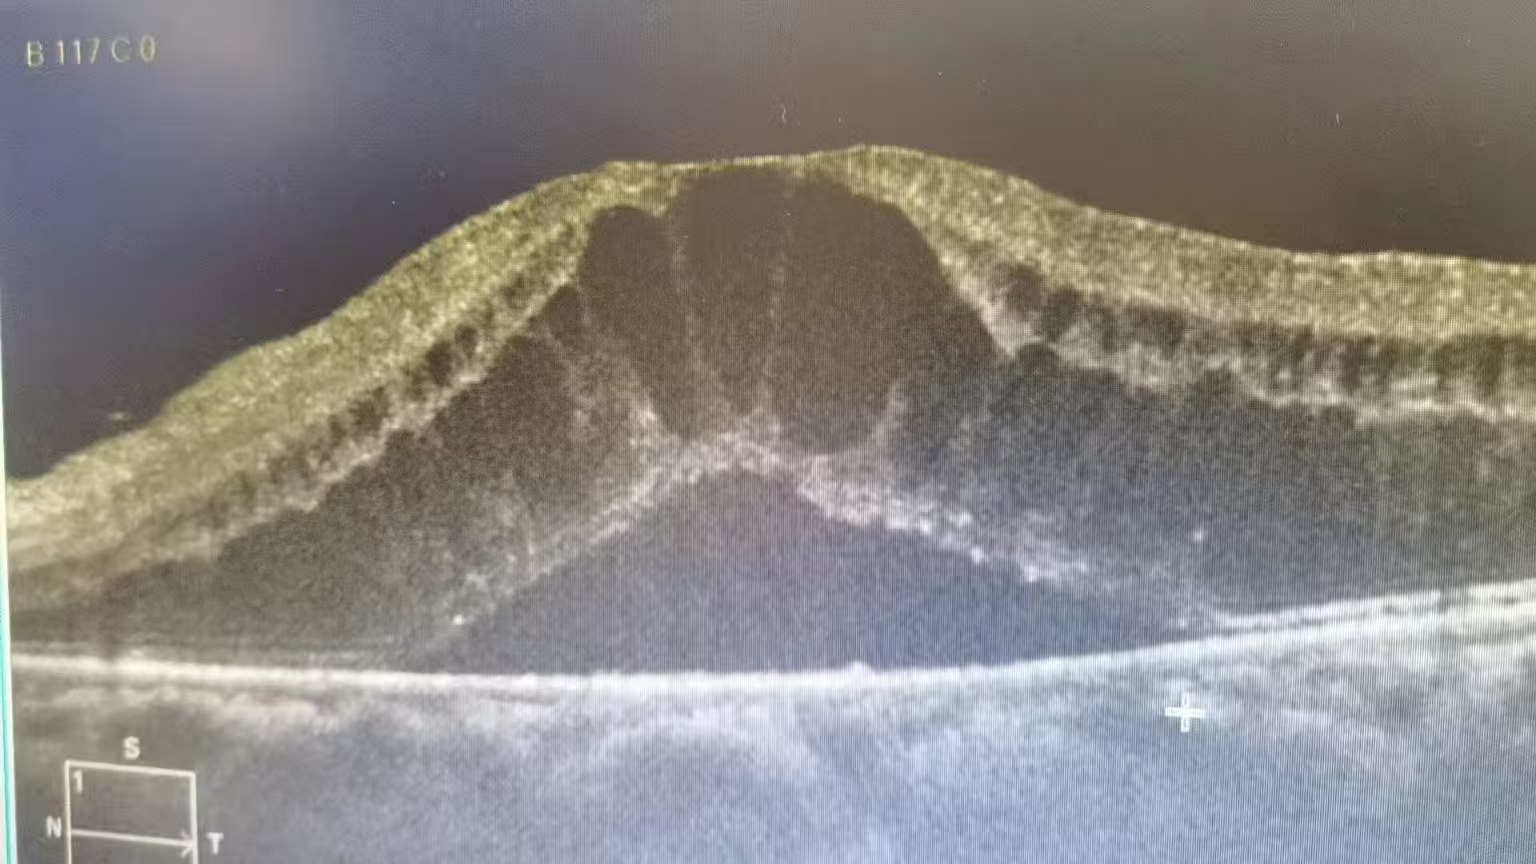

很多患者对“眼内注药”心存顾虑,实则这项操作已十分成熟,全程10分钟左右且无明显痛感。术前通过视力检查、眼压测量、OCT等有效评估,排除禁忌;眼部清洁后滴用抗生素眼药水和表面麻醉,无需注射麻药;术中在显微镜引导下,用直径约0.3毫米极细针头从眼球安心区域注入药物,仅1-2分钟,患者多只有轻微异物感;术后观察30分钟-1小时,无异常回家,遵医嘱滴1-2周抗生素眼药水。

黄斑水肿并非“快速到位”,抗VEGF药物常规疗程为“首月每月1次,连续3次”,后续需通过复查调整间隔,部分患者需长期维持。术后1-2周要避免揉眼、游泳、污水入眼,不做剧烈运动和负重,严格遵医嘱用药,若出现眼红加重、视力骤降等异常需立即就医。